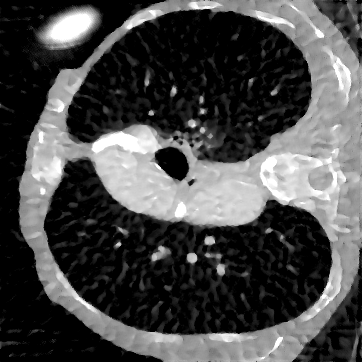

Deep learning-based image reconstruction approaches have demonstrated impressive empirical performance in many imaging modalities. These approaches generally require a large amount of high-quality training data, which is often not available. To circumvent this issue, we develop a novel unsupervised knowledge-transfer paradigm for learned iterative reconstruction within a Bayesian framework. The proposed approach learns an iterative reconstruction network in two phases. The first phase trains a reconstruction network with a set of ordered pairs comprising of ground truth images and measurement data. The second phase fine-tunes the pretrained network to the measurement data without supervision. Furthermore, the framework delivers uncertainty information over the reconstructed image. We present extensive experimental results on low-dose and sparse-view computed tomography, showing that the proposed framework significantly improves reconstruction quality not only visually, but also quantitatively in terms of PSNR and SSIM, and is competitive with several state-of-the-art supervised and unsupervised reconstruction techniques.